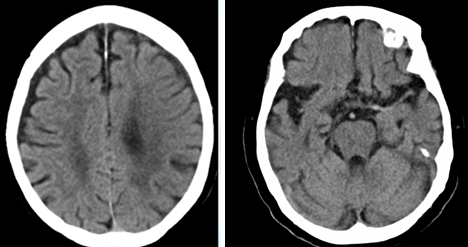

88歳女性。3時間半前から右上下肢の動かしにくさを自覚し、家族に連れられて来院。

頭部CT施行。

左脳に脳溝の狭小化を伴う浮腫性変化

中大脳動脈領域に低吸収域

左中大脳動脈に血栓疑われる

→急性期脳梗塞